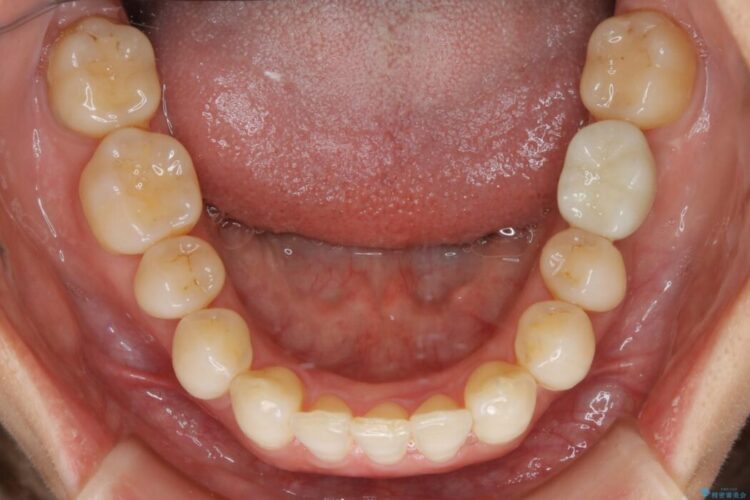

噛み合わせも改善され、一番最初の目的であった歯列もきれいに整いご満足いただけました。